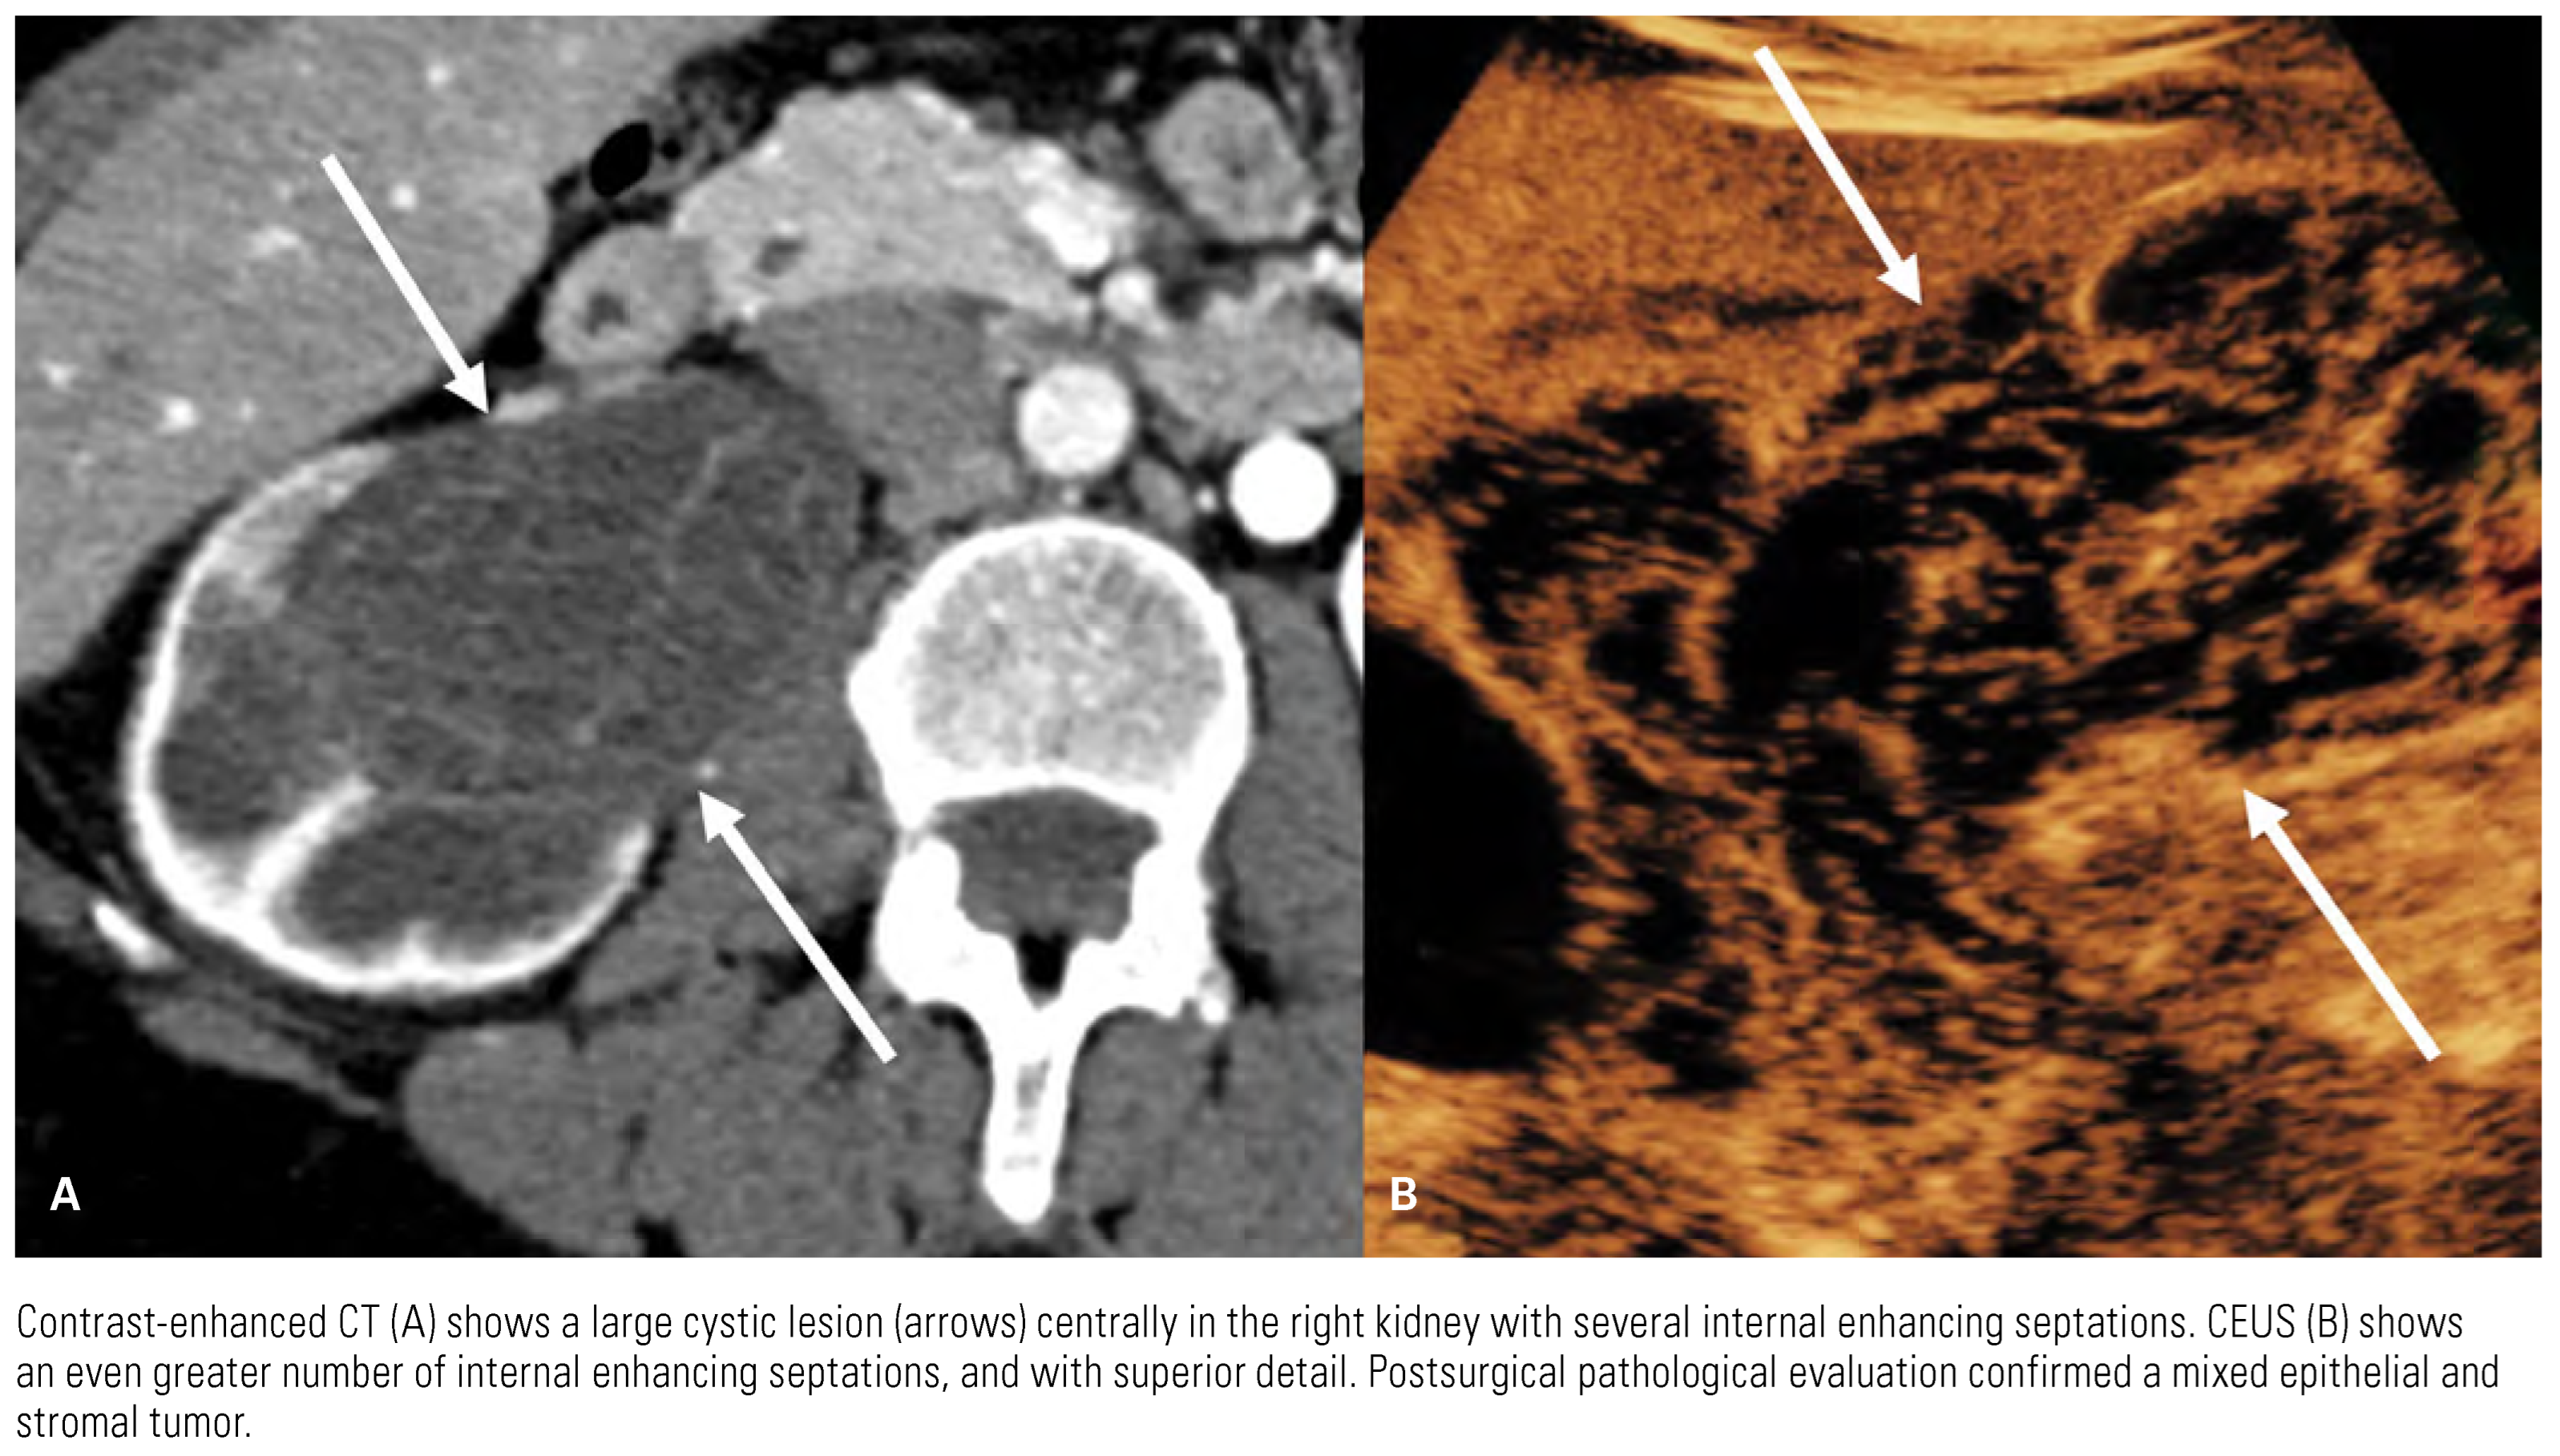

Detection and Diagnosis

Imaging Features of Common Subtypes of RCC